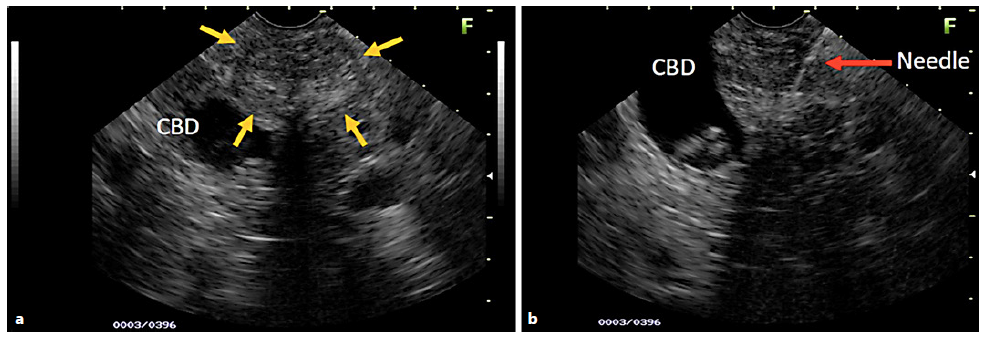

Fig. 1 a) EUS image of a young patient with a hypoechoic area (yellow arrows), also heterogeneous with imprecise limits and a microcystic component, right next to the common bile duct (CBD) with stones inside (a, b). The EUS images suspected SPN. B) Moment of the EUS-FNA (red arrow), with the 22-G needle positioned in the center of the lesion. The biopsy revealed chronic inflammatory process without evidence of SPN.